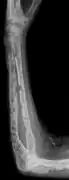

The diagnostic examination of a person with suspected multiple myeloma typically includes a skeletal survey. This is a series of X-rays of the skull, axial skeleton, and proximal long bones. Myeloma activity sometimes appears as "lytic lesions" (with local disappearance of normal bone due to resorption) or as "punched-out lesions" on the skull X-ray ("raindrop skull"). Lesions may also be sclerotic, which is seen as radiodense.[70] Overall, the radiodensity of myeloma is between −30 and 120 Hounsfield units (HU).[71] Magnetic resonance imaging is more sensitive than simple X-rays in the detection of lytic lesions, and may supersede a skeletal survey, especially when vertebral disease is suspected. Occasionally, a CT scan is performed to measure the size of soft-tissue plasmacytomas. Bone scans are typically not of any additional value in the workup of people with myeloma (no new bone formation; lytic lesions not well visualized on bone scan).

X-ray of the forearm, with lytic lesions